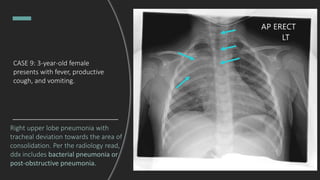

CASE 9: 3-year-old female

presents with fever, productive

cough, and vomiting.

Interpret this chest X-ray.

Right upper lobe pneumonia with

tracheal deviation towards the area of

consolidation. Per the radiology read,

ddx includes bacterial pneumonia or

post-obstructive pneumonia.